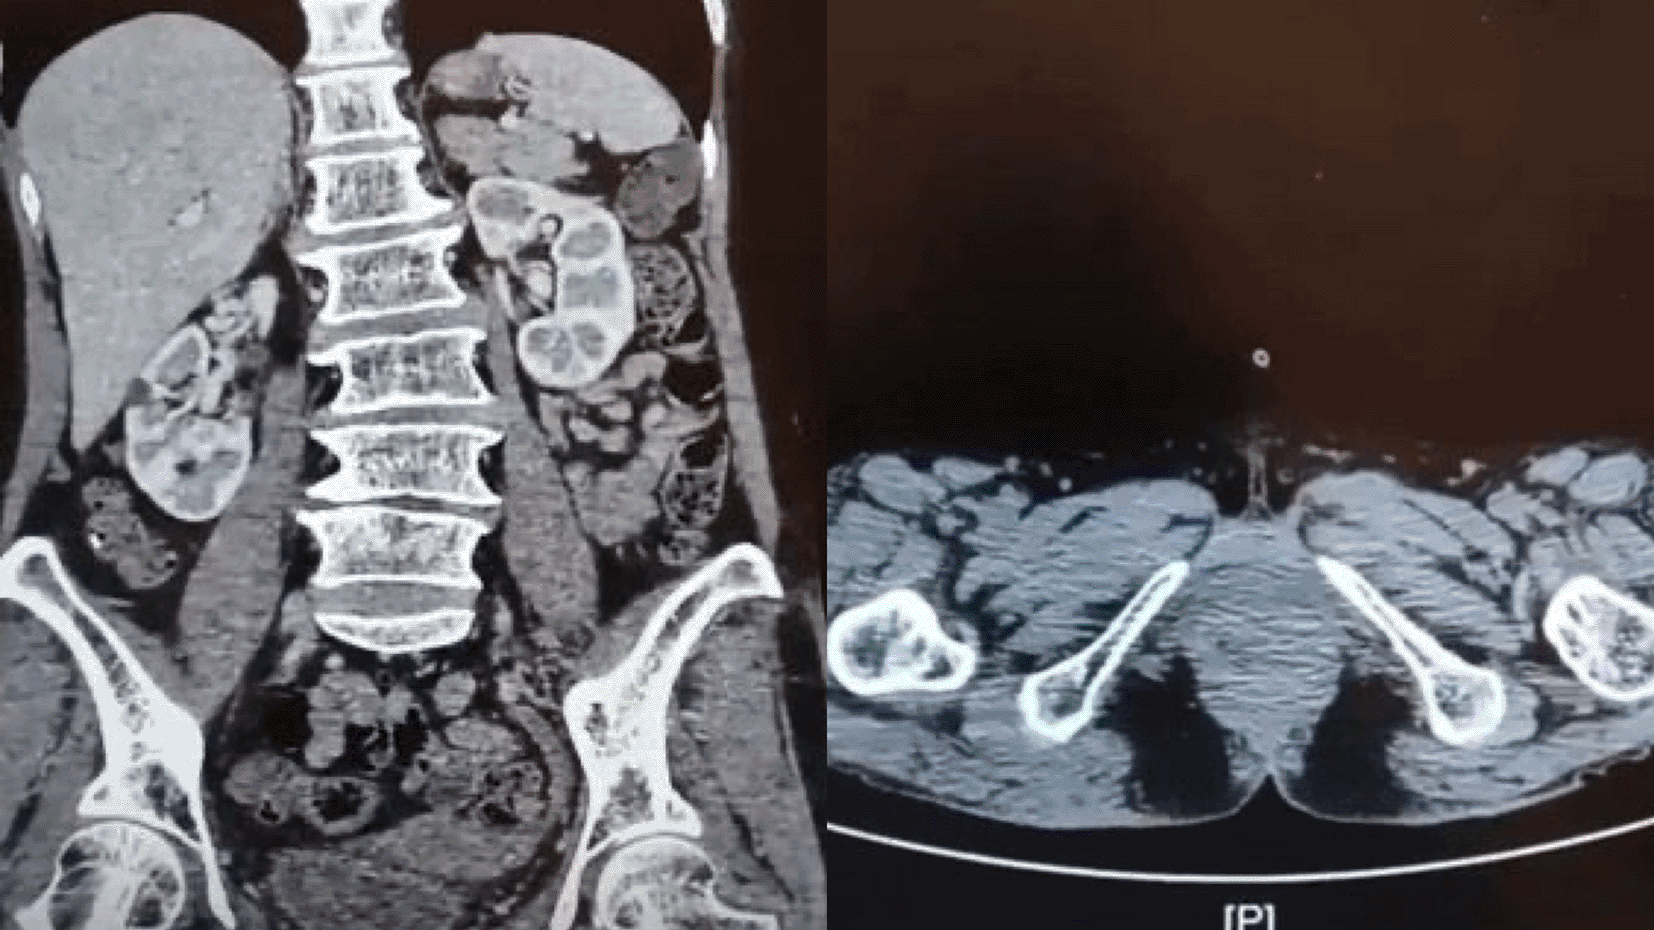

A 65-year-old Southeast Asian woman was presented to the emergency department with urinary retention since 4 hours before admission. The patient had a history of weak stream and straining for 6 months prior. The patient denied any history of hematuria and vaginal spotting. She denied any previous surgery related to the pelvic and history of cerebrovascular disease. Her physical examination shown a full bladder and large mass covering the urethral orifice without involvement of the vagina ( Figure 1). The patient then underwent percutaneous cystostomy. A contrast-enhanced CT scan of abdomen and pelvis then performed subsequently which revealed a suspected malignant mass in the entire length of urethra, with no inguinal lymph nodes enlargement and no evidence of metastases ( Figure 2). The staging based on CT scan was cT3N0M0.